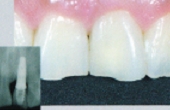

■CASE-1.(前装冠)

Sinfonyは前装冠であっても硬質レジン特有のツヤの消失が少なく、透明感が持続します。

[術前] [装着]